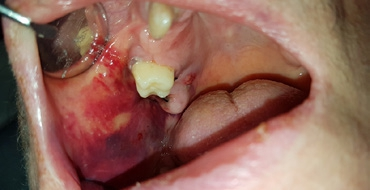

Die eingebrachte Verbandsplatte sollte je nach Umfang des zahnärztlich- chirurgischen Eingriffs mindestens bis zum Nachfolgetag, meist aber über 48 Stunden im Mund des Patienten belassen werden. Genauso verhält es sich bei Verbandsplatten nach einer subgingivalen Parodontitistherapie (Abb. 3). Diese können frühestens am nächsten Tag bei der Wundkontrolle entnommen, gereinigt und evtl. erneut eingebracht werden. Am Tag der Wundkontrolle sollte in der Regel eine blutungsfreie Wunde erkennbar sein. Häufig ist schon die Bildung eines Hämatoms sichtbar (Abb. 4 u. 5).